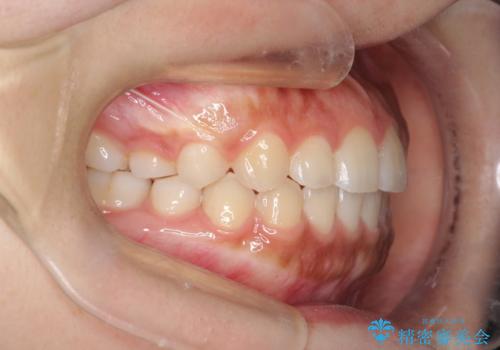

インビザライン 前歯のがたつきを目立たず矯正

- 前歯のがたつきが気になるとのことで来院されました。

インビザラインにて治療を行いました。

わずかに歯と歯の間に隙間を作り、歯列矯正を行いました。

マウスピースをしっかりと使用していただけたので、スムーズに治療を終了することができました。